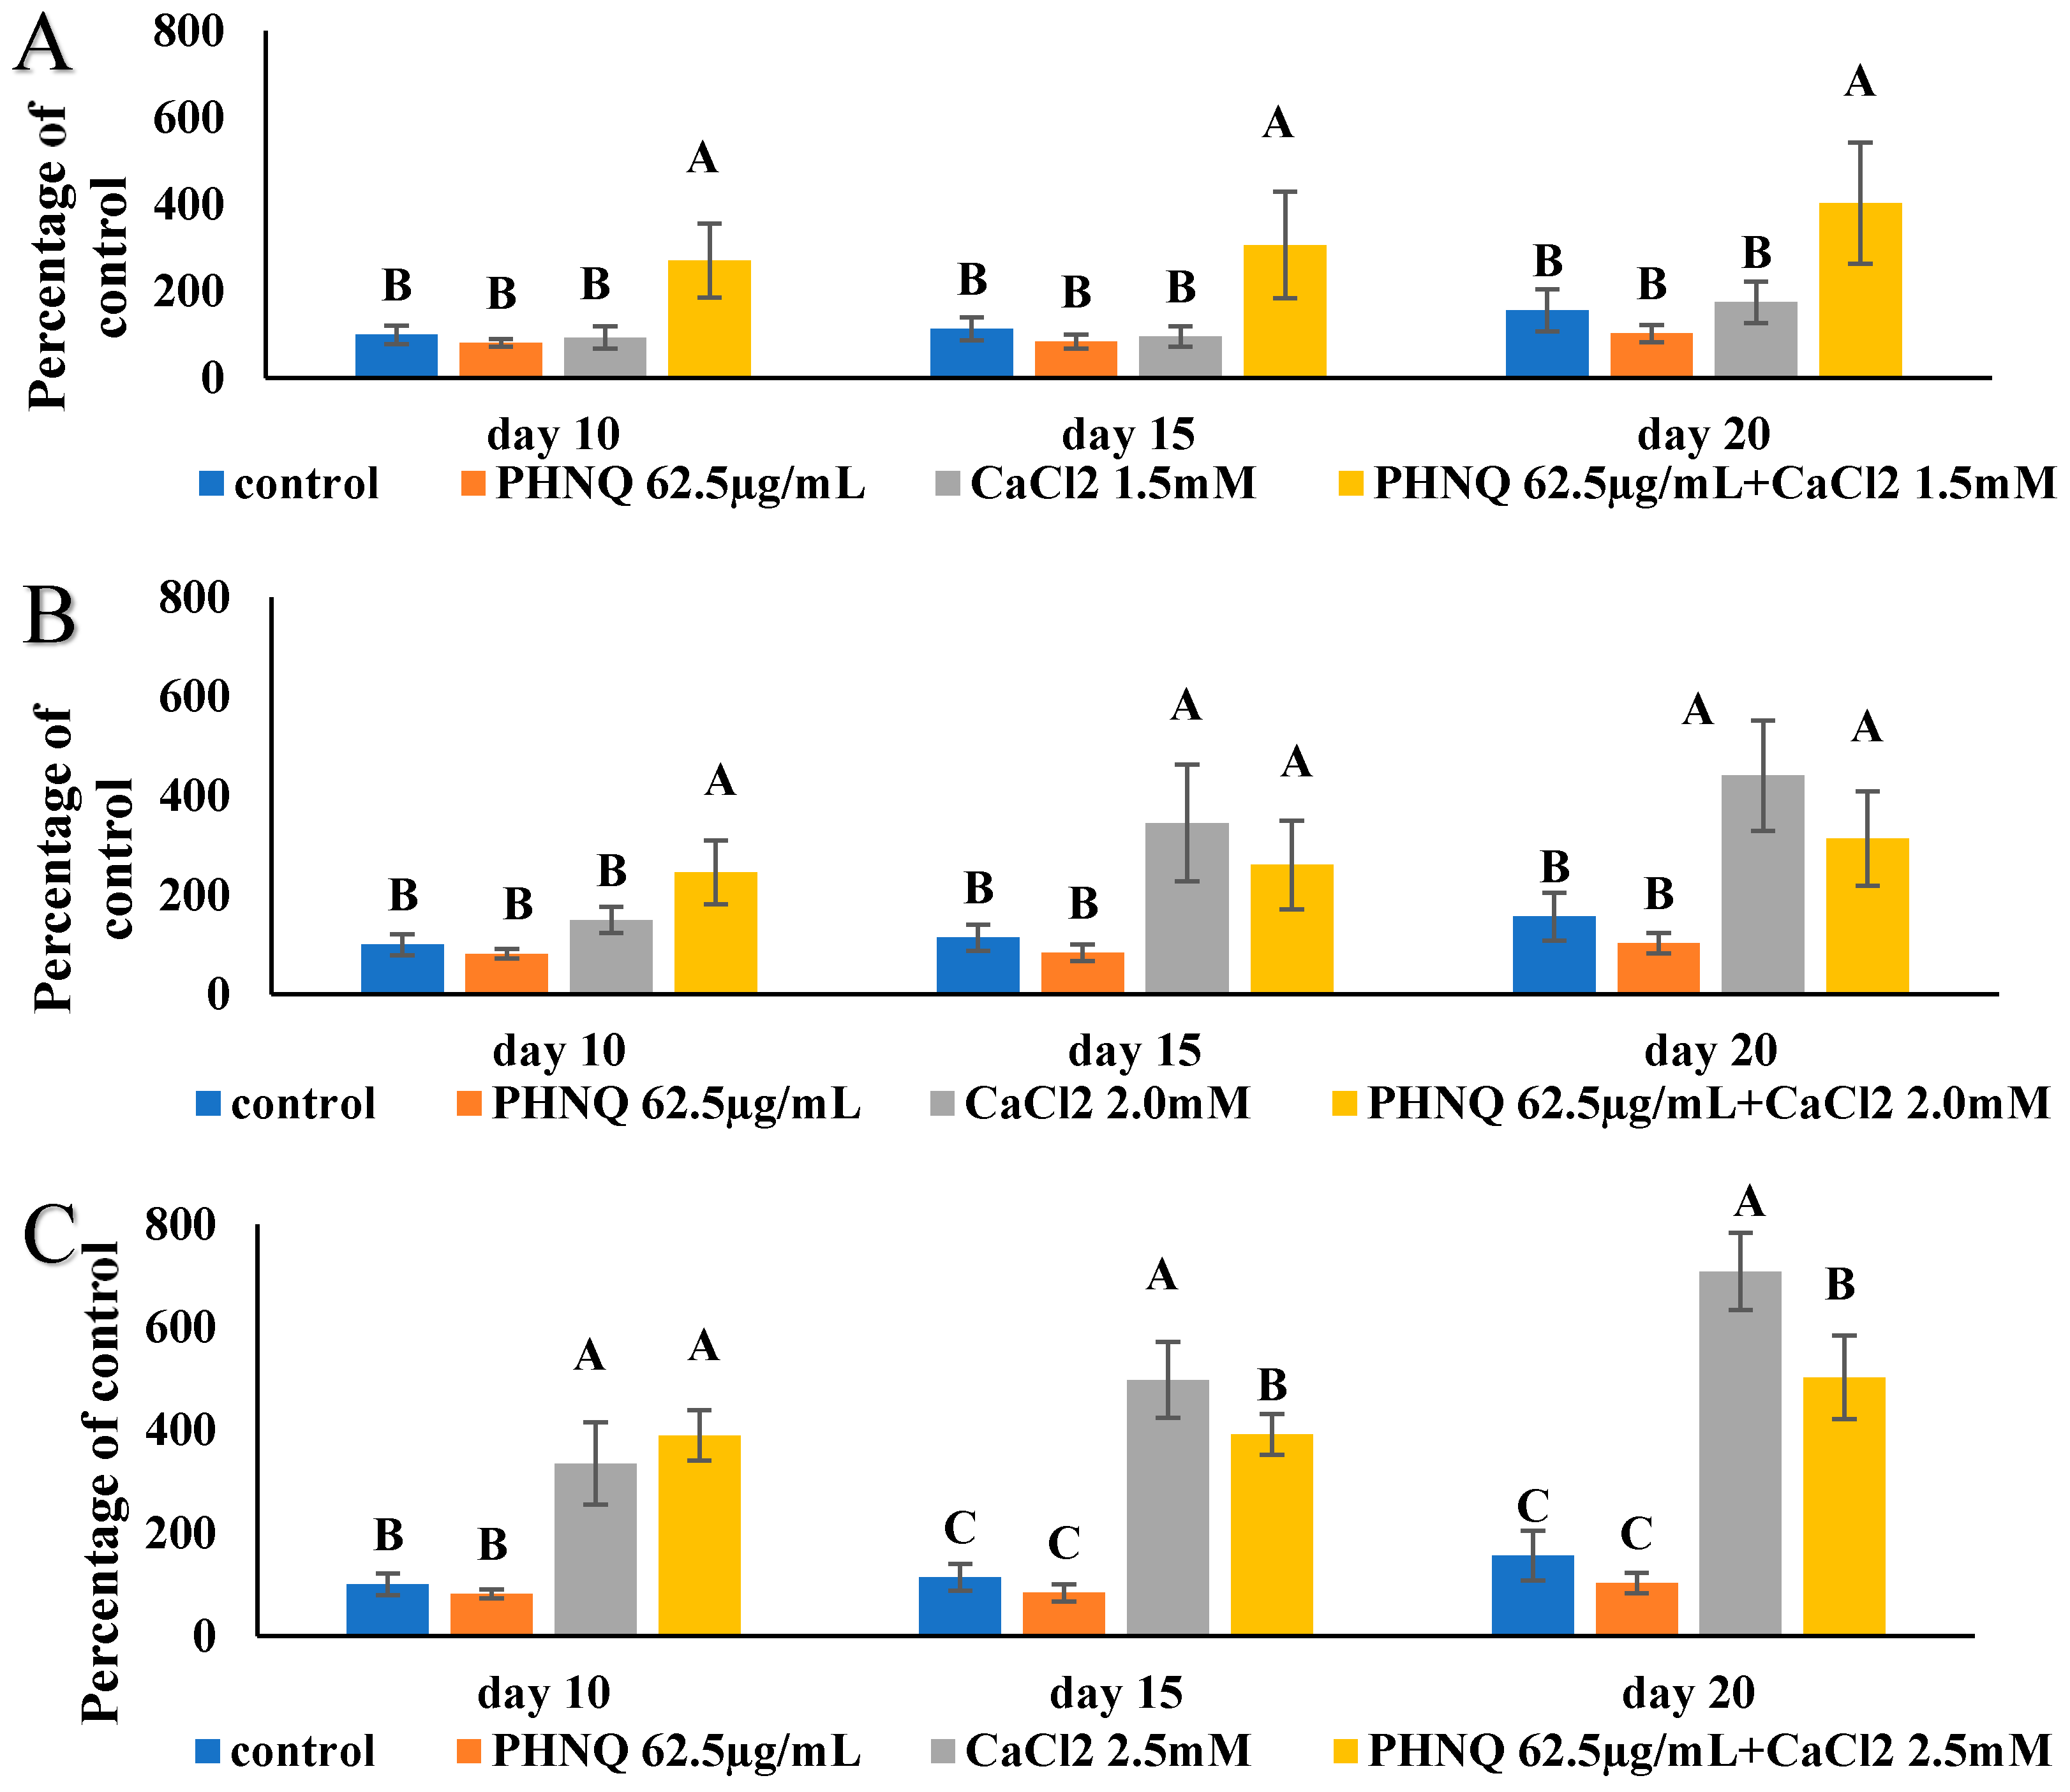

2.7. Effect of PHNQ on Mineralization in the Presence of CaCl2